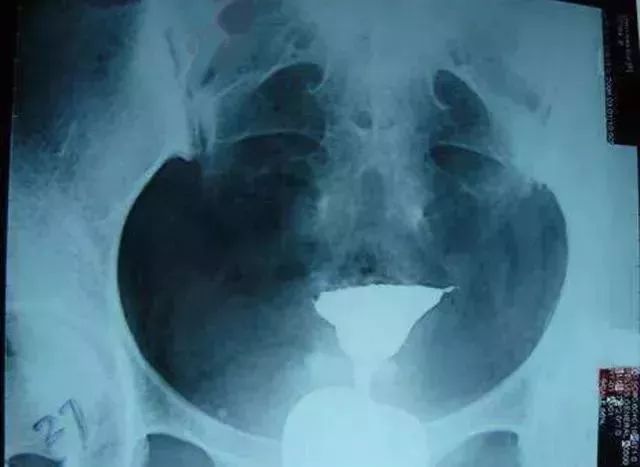

输卵管积水

造影片的表现是一侧或双侧输卵管远端增粗、膨大,呈“腊肠状”。这是由于输卵管远端粘连不通导致输卵管内造影剂不能溢出所导致。所以,输卵管积水的前提是输卵管不通。如果造影片显示输卵管伞端有造影剂溢出就不是积水。输卵管积水会影响试管婴儿的成功率,建议在胚胎移植前先处理输卵管积水。